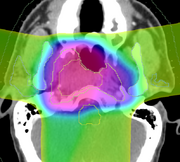

Plan review using dose volume histograms

Evaluation of the dosimetry results will be performed using techniques that are well established in the radiotherapy field, such as isodose evaluation and dose volume histograms (DVHs). Although it would be possible to export images from 3D Slicer back into commercial systems to perform this analysis, it is a much better workflow to do the analysis within the 3D Slicer software. The goal of this project is therefore to provide sufficient capabilities within the 3D Slicer environment, so that radiotherapy experts can perform plan review and plan comparison between a nominal treatment plan and an adaptive plan. The minimum set of useful comparison tools that we have identified to achieve this goal are isodose views, DVH generation, structure set manipulation, dose differencing, and gamma analysis.